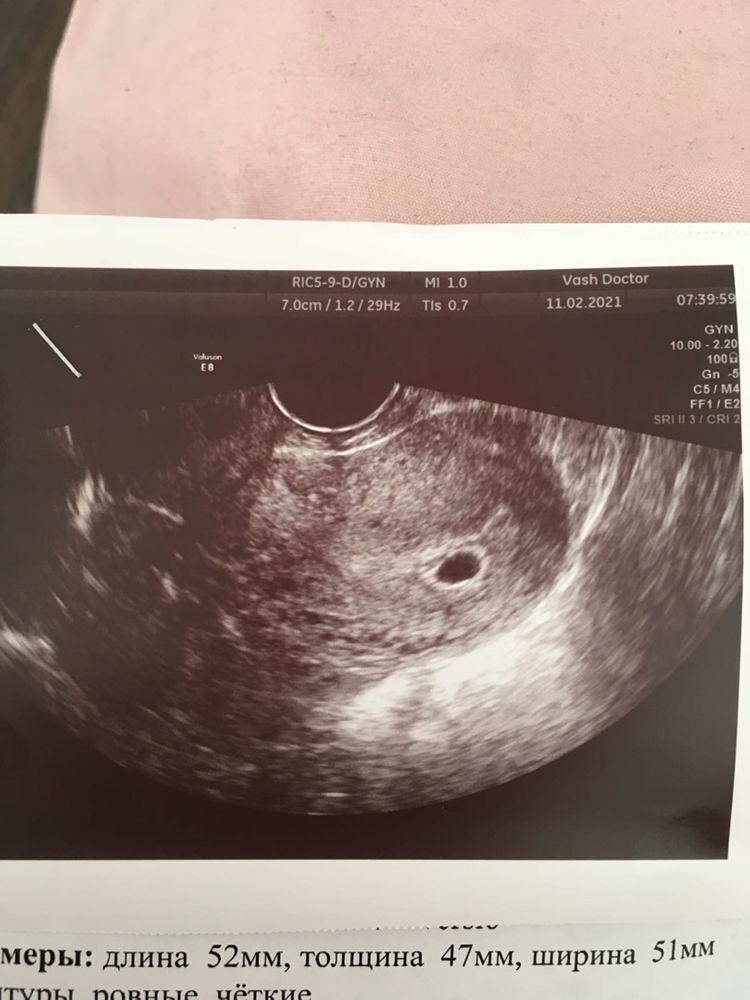

Узи определение беременности

Единственное о чем говорит данное узи это то что у вас маточная беременность, а нормальная она или нет, это уже будет понятно через пару недель

Сказали, что беременность отстает и через неделю прийти, также сдавать хгч в динамике🤷‍♀️

не переживайте, если с эмбрионом все ок то все и будет хорошо, а если что-то не так на генетическом уровне то, к сожалению, даже развиваются срок в срок но сохранить беременность не удается. У меня на сроке 7 недель по узи было 6, тоже переживала, но к скринингу в 12 все уже было четко)) Пусть у вас с малышом все будет хорошо!

Все хорошо.у вас беременость 4 недели